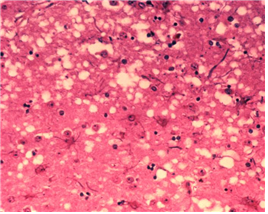

프리온에 의한 질병은 병변 조직에 스펀지처럼 구멍이 뚫린 듯한 모습이 관찰된다. 사진 출처: WIKIPEDIA 프리온(prion)은 단백질(protein)과 바이러스 입자(virion)의 합성어로 바이러스는 핵산과 단백질로 이루어졌지만 프리온은 단백질만으로 이루어져 있어 붙여진 이름입니다. 프리온에 의한 질병은 변형 프리온이 사람이나 동물에 축적되어 발생하게 됩니다. 아콥병(Creutzfeldt-Jakob disease)은 이와 같은 변형 프리온에 의한 질환으로 해면성 뇌병증에 감염된 소고기를 먹으면 발병할 수 있다는 것이 알려져 있습니다. 프리온에 의한 질병은 뇌와 같이 중추신경계에만 발생하며 병변 부위에 구멍이 뚫려 스펀지 같은 모양을 보이는 것이 특징입니다. 또한 다른 감염성 질환과 달리 특이적인 염증 반응이 일으키지 않습니다. 프리온에 의한 질병은 길게는 수년까지 잠복기를 가지고 있지만 한 번 발병하면 100% 사망에 이른다고 합니다. 안타깝게도 아직까지 변형 프리온이 생기는 과정에 대해 명확히 규명되어 있지 않으며 백신과 치료법 또한 아직 개발되어 있지 않습니다. 지금까지 우리 몸에 감염을 일으키는 병원체에 대해 정리해 봤습니다. 병원성 바이러스, 세균, 곰팡이는 우리 몸에 유해하여 질병을 야기한다는 공통점을 가지고 있지만 병을 일으키는 원인도 증식 방법도 치료법도 모두 다릅니다. 이 글을 통해 다양한 병원체로 인한 감염성 질환들을 이해하는데 조금이나마 도움이 되셨길 바랍니다. References 1. Neil A. Campbell, Jane B. Reece, Lisa A. Urry et al., 2016, 캠벨 생명과학, 10판 2. 의협신문 https://bit.ly/2KBsi1J 3. Merck Sharp & Dohme Corp https://msdmnls.co/2Sa9BWK 4. 위키피디아 https://bit.ly/2VWQYa2